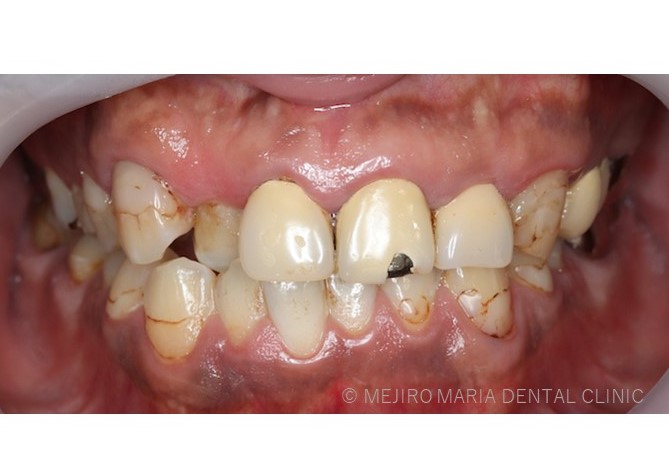

レジンと歯の境目に褐線(かっせん)と言われる茶色い着色が多く確認できる、また前歯部のレジン冠も色が変色している。